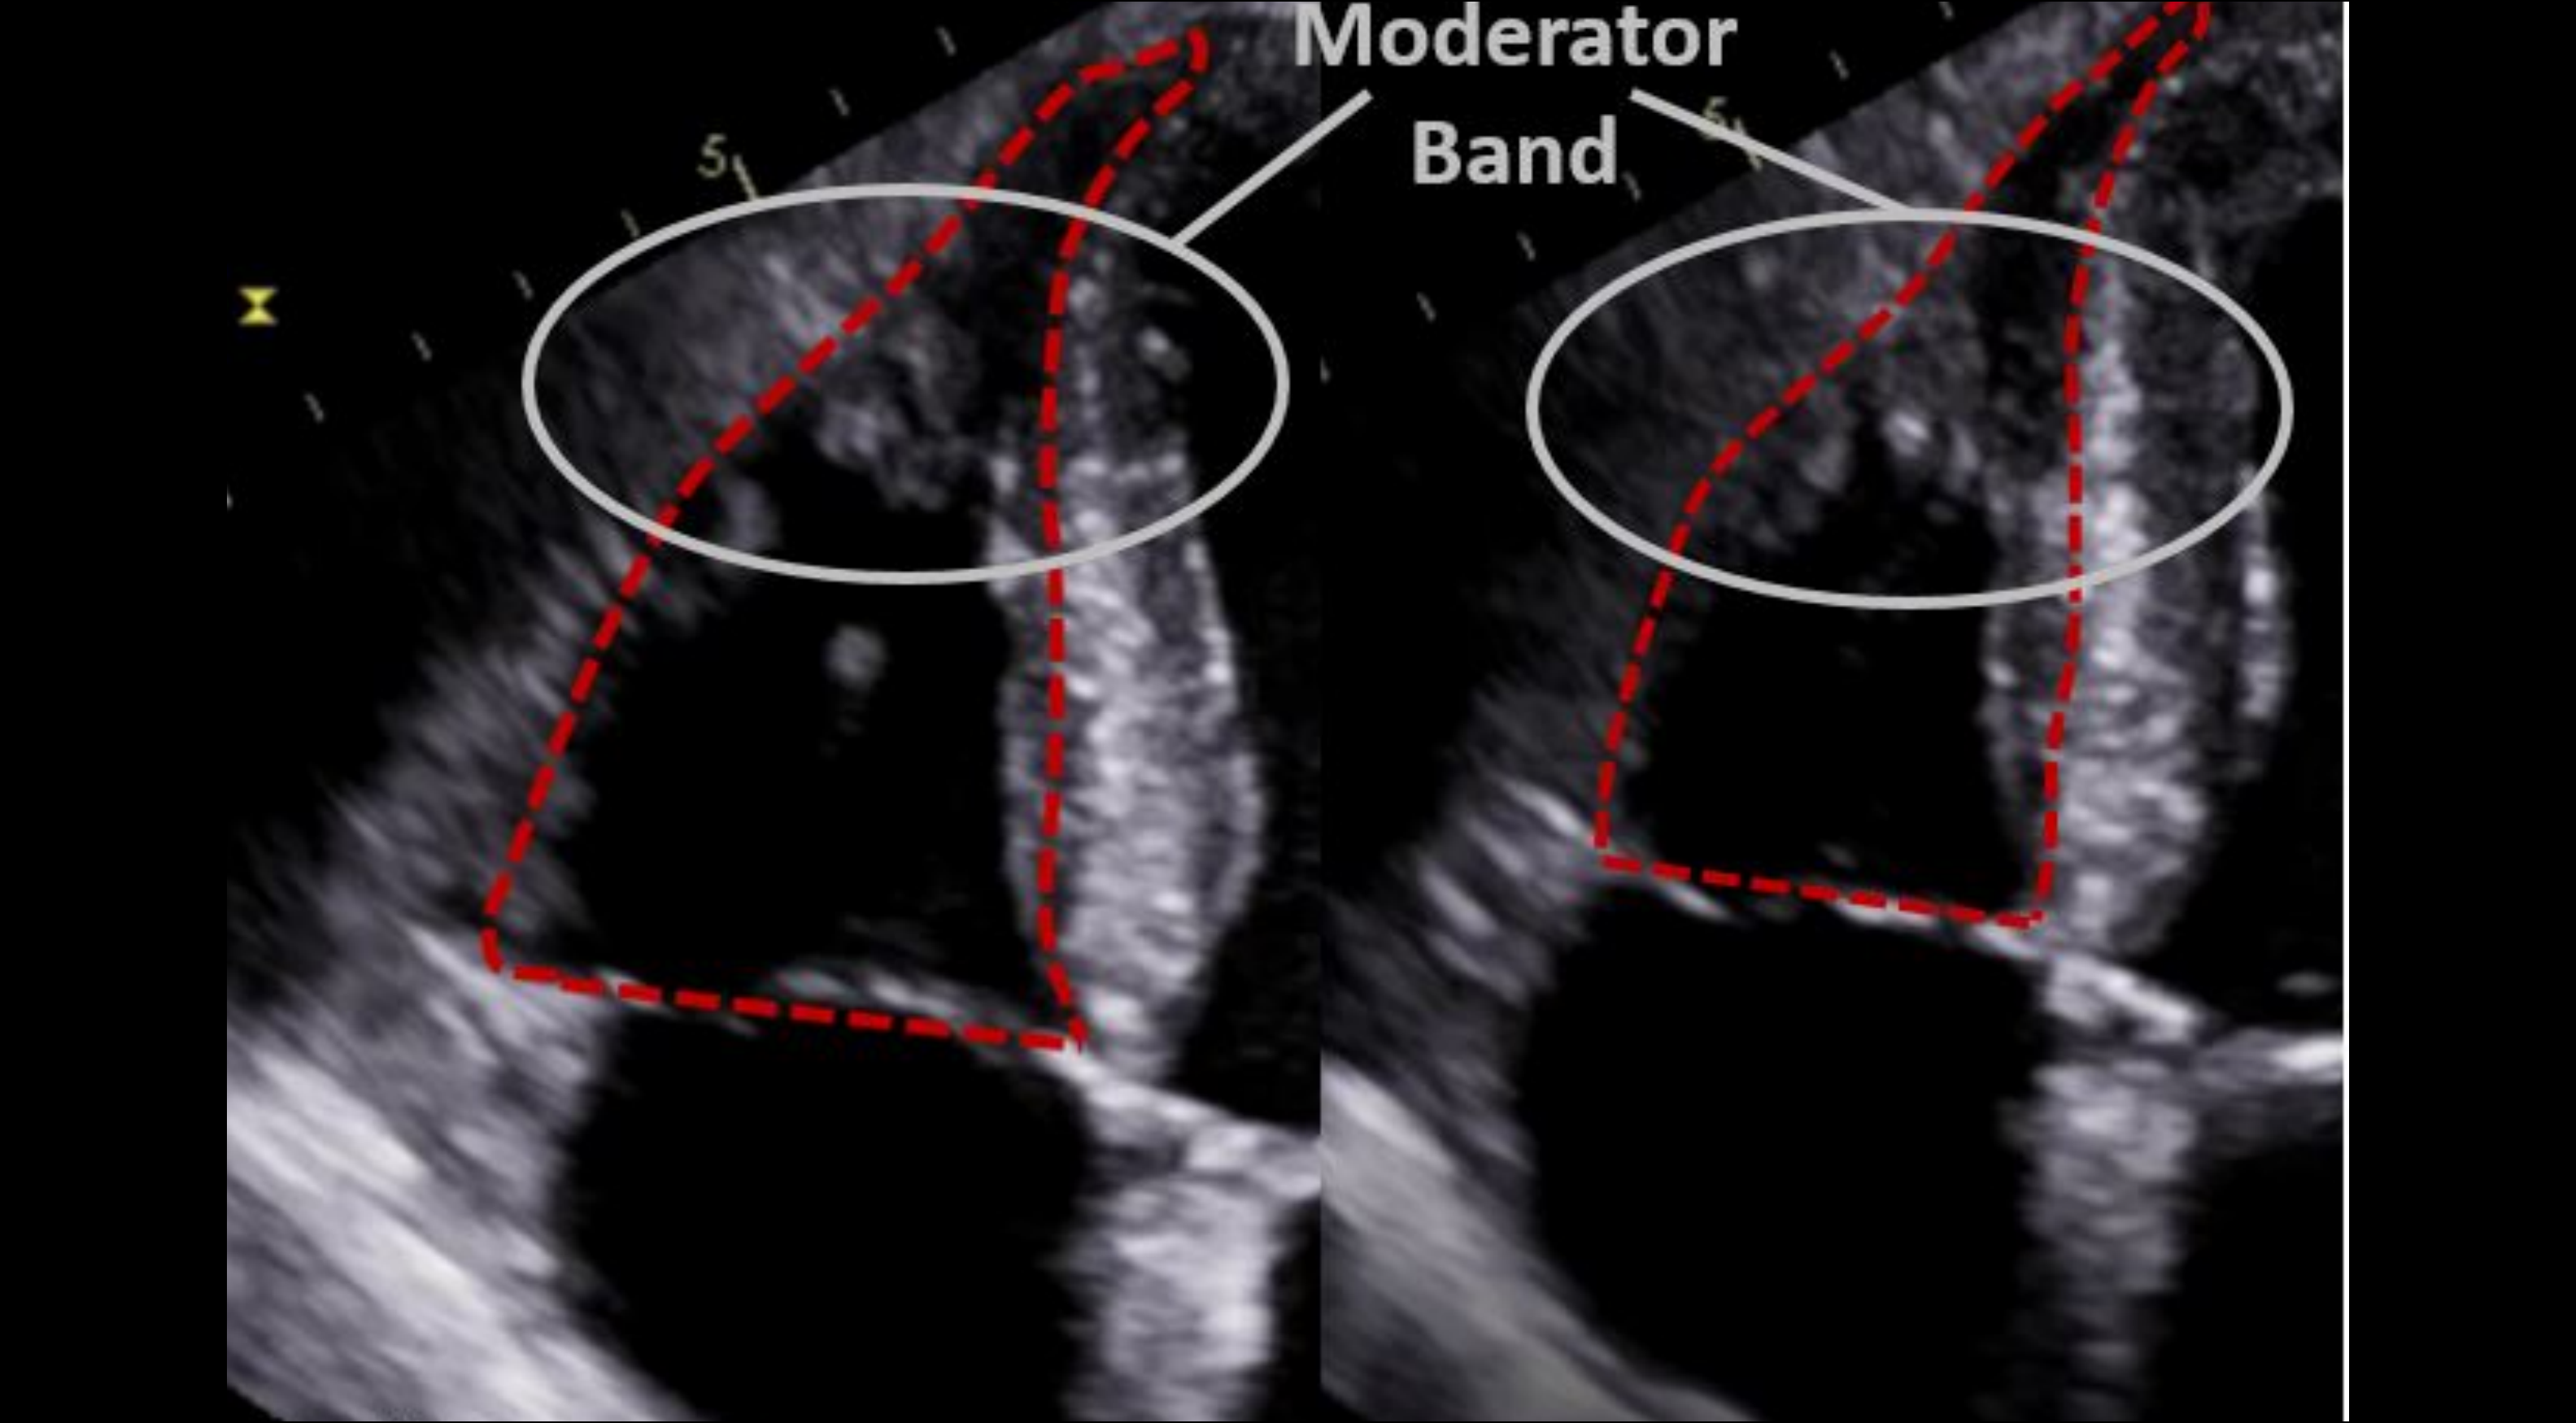

From www.emra.org